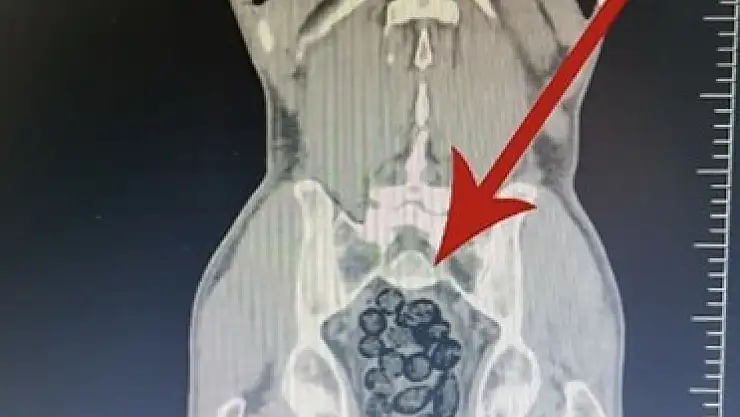

Yapılan tıbbi kontroller sonucunda yabancı uyruklu şahsın midesinde 64 parça halinde paketlenmiş uyuşturucu madde bulunduğu belirlendi. Ele geçirilen maddenin toplam 472 gram metamfetamin olduğu tespit edildi.

Gözaltına alınan şüphelinin midesindeki uyuşturucu maddeler sağlık ekipleri tarafından çıkarıldı. Emniyetteki işlemleri tamamlanan şahıs, adliyeye sevk edildi. Mahkemeye çıkarılan zanlı, tutuklanarak cezaevine gönderildi.